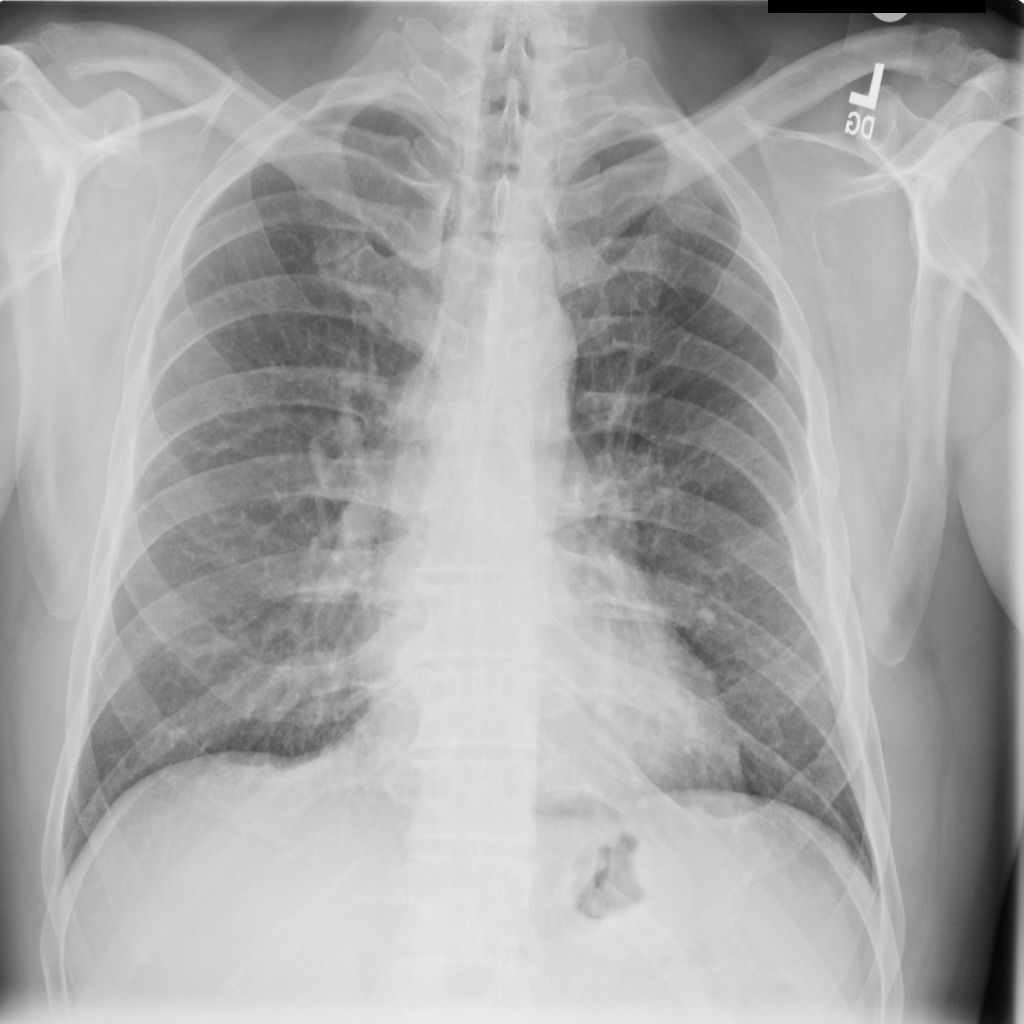

PAT-250B · IMG-000Nodule

PAT-250B · IMG-000

PA